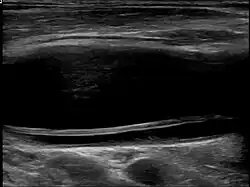

Carotid artery dissection can occur spontaneously or be triggered by trauma, including minor injuries, certain medical conditions, or activities that involve neck movement. It is a leading cause of stroke in young and middle-aged adults. The condition is typically diagnosed through imaging studies, such as ultrasound, magnetic resonance imaging (MRI), magnetic resonance angiography (MRA), or computed tomography angiography (CTA), which help visualize the blood vessels and detect abnormalities.